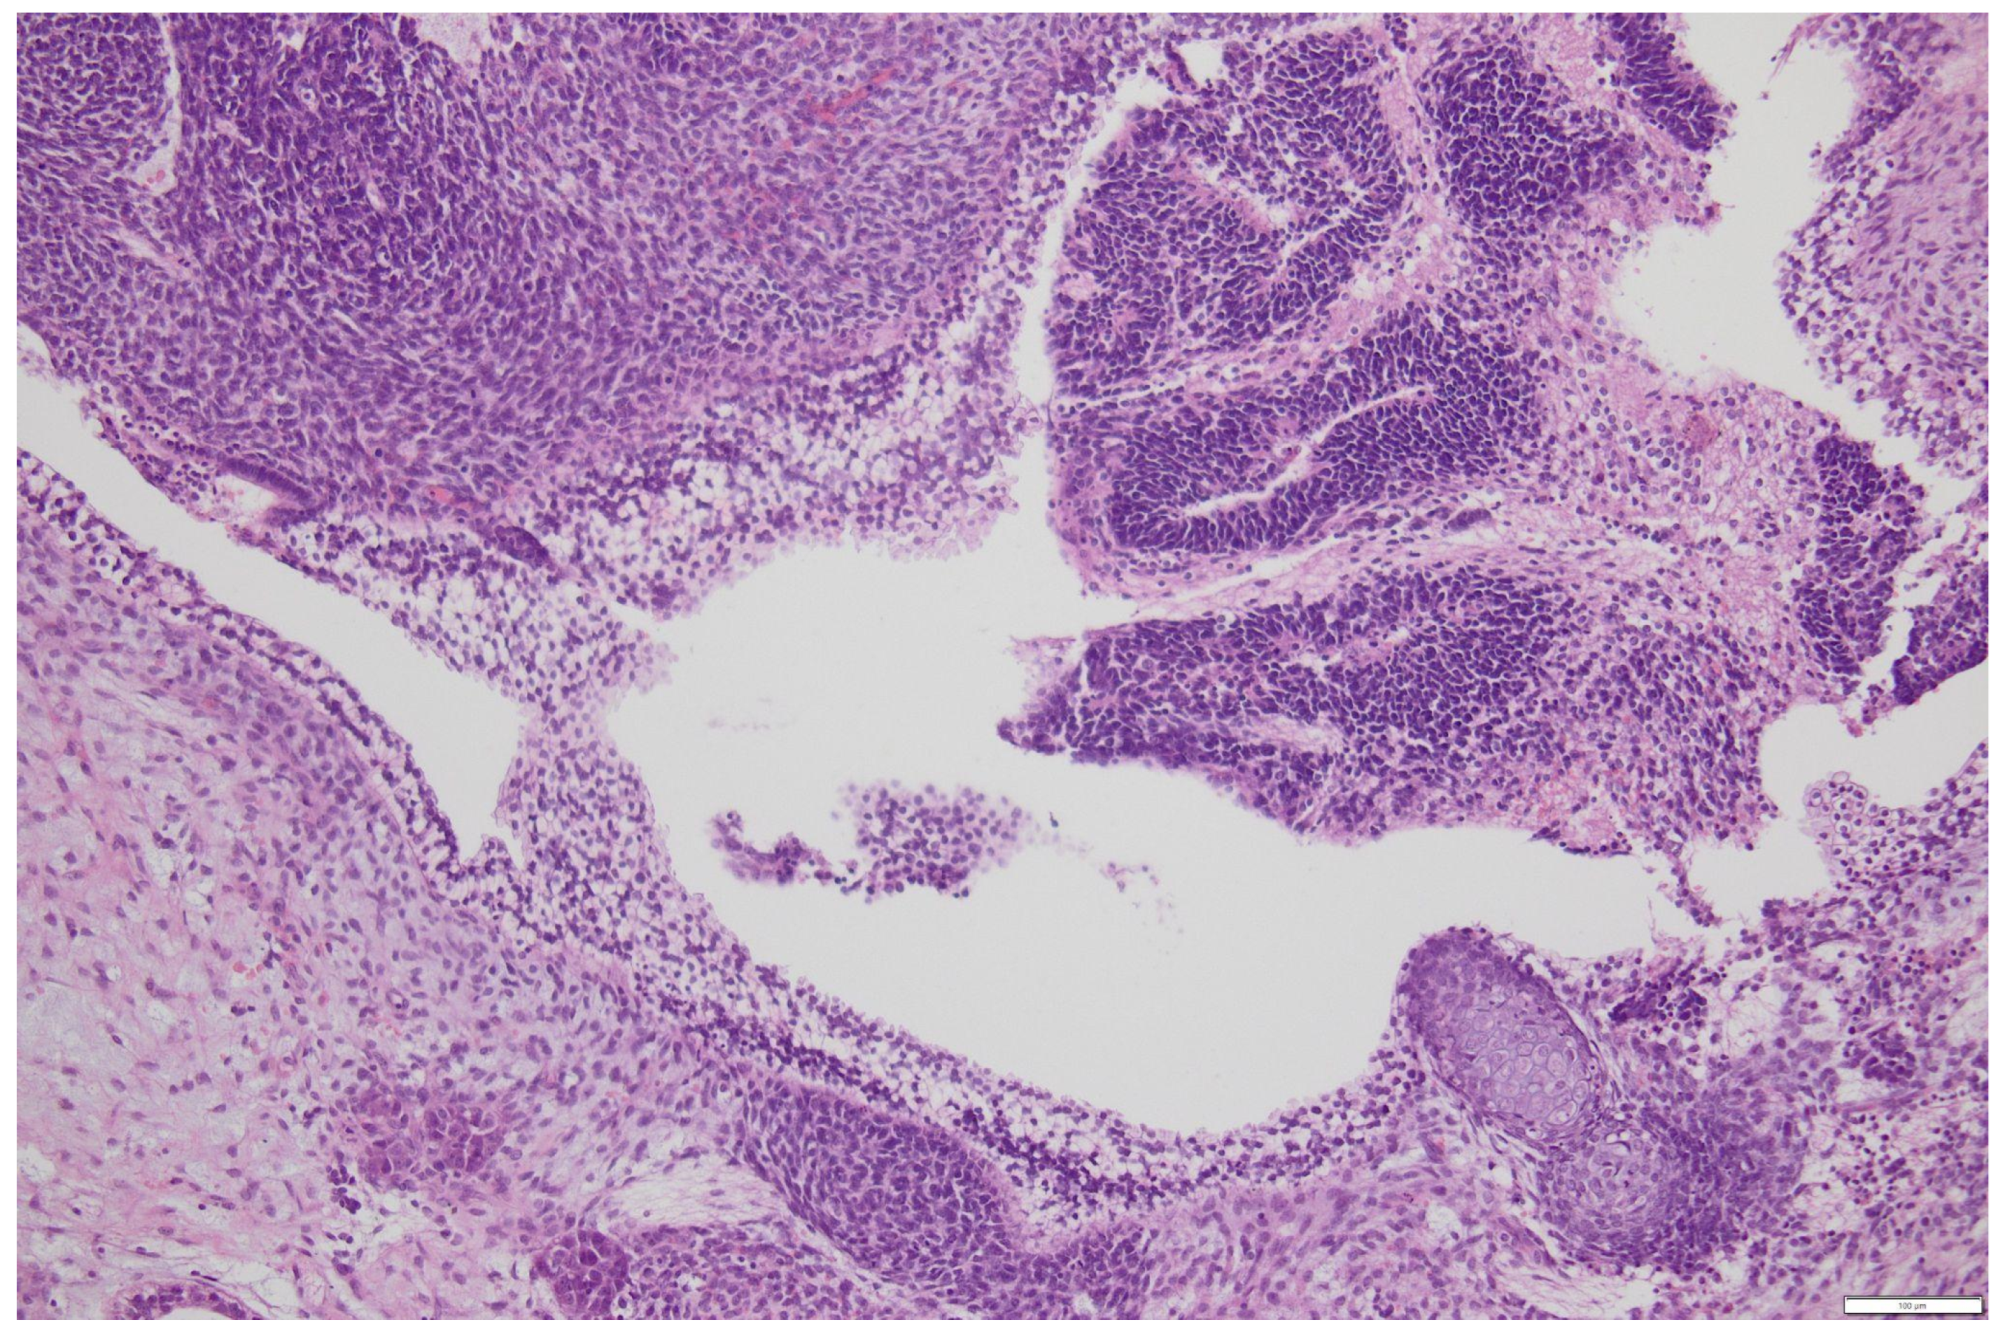

3. Immature Teratomas

3.1. Diagnosis

3.2. Prognostic Factors

- Grade 1: <1 low power field (using a 4× objective and a 10× lens, 40× of magnification) per slide;

- Grade 2: ≥1 but <3 low power fields in any slide;

- Grade 3: ≥3 low-power fields in any slide.